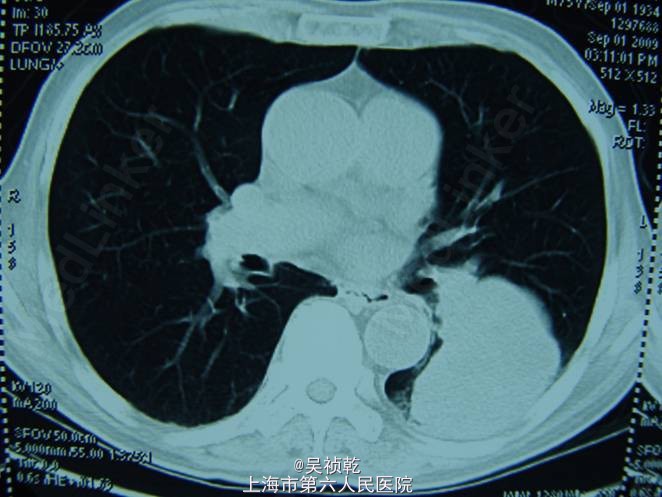

查体:浅表淋巴结(-)既往无重大疾病,体重下降5kg,肿瘤CEA>1500 ug/L。胸部CT :左下肺占位,考虑转移。上腹部CT :肝脏多发转移。盆腔CT :直肠肿物,伴不全肠梗阻。

术前诊断:直肠癌伴肝肺转移(肝脏多发,肺单发) 行直肠癌TME手术:术中探查:肝脏多发转移结节,最大者4cm, 无腹水及腹盆腔种植结节; 直肠肿瘤距肛门8cm,侵犯浆膜外脂肪组织。 病理:溃疡型管状腺癌II级,4.5*3.5*2cm,侵至肠壁全层,达肠周脂肪组织,肠周淋巴结转移: 6/12,肠系膜动脉根部0/2淋巴管(+)神经周围(+)血管(+)。K-ras检测:野生型 术后行化疗方案为:FOLFOX 4+Cetuximab (q2wk * 6次) 后评估肿瘤部分缓解,6次化疗结束后改为XELOX / q3wk*6次,评估肿瘤无进展。 下图可见复查的影响学资料相比化疗前肿瘤有明显缩小。